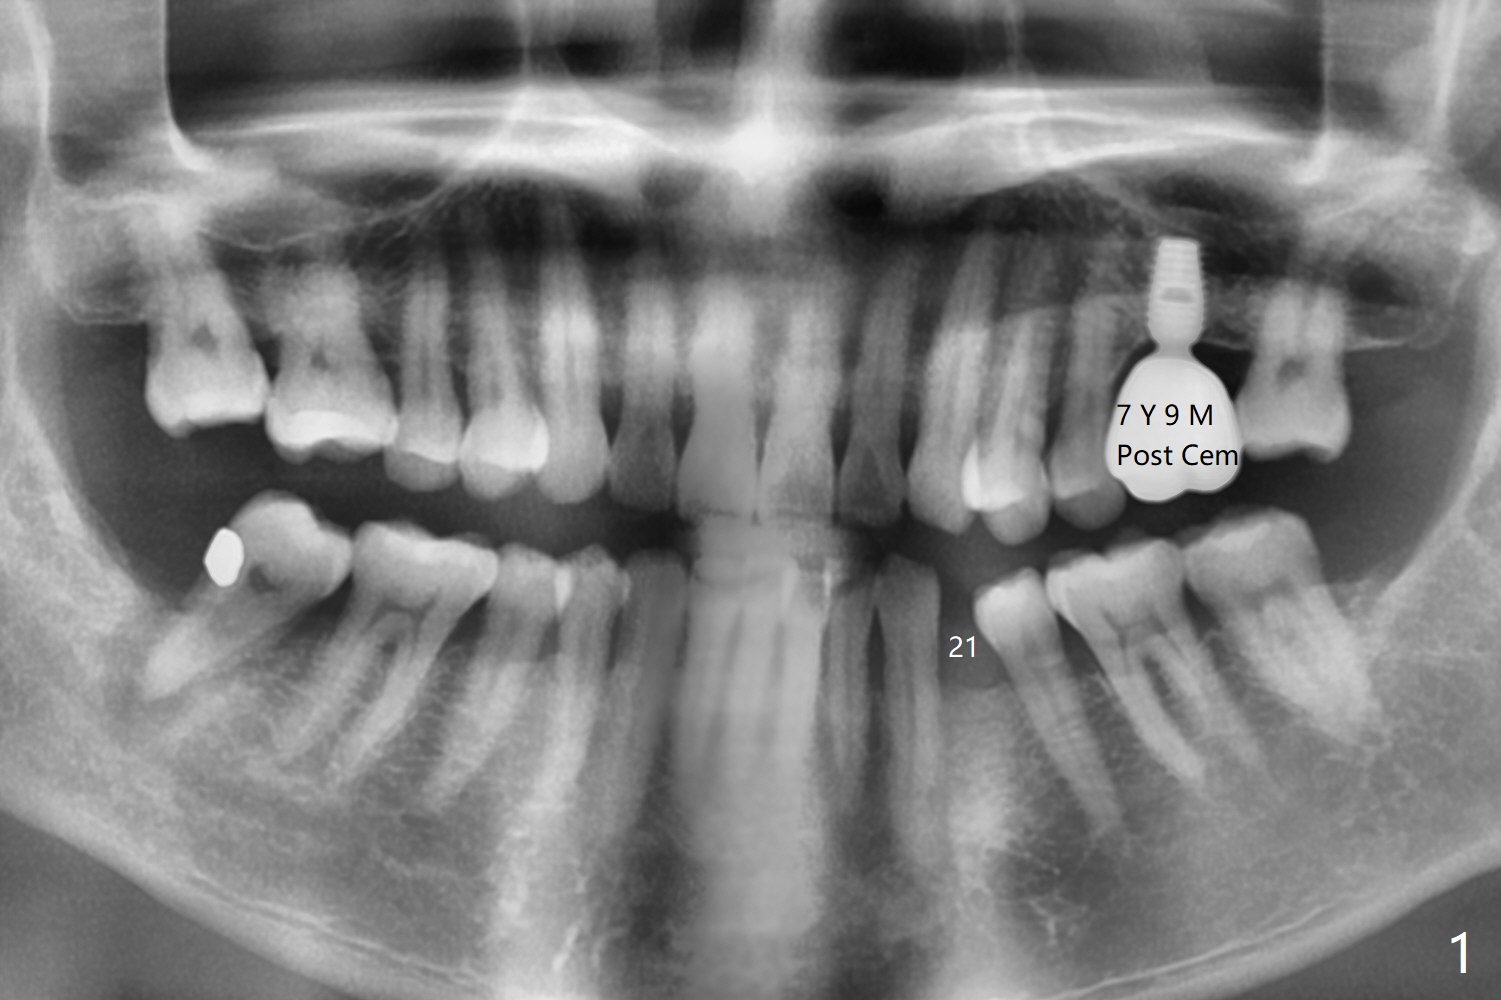

63岁男左上第一磨牙种植牙冠粘固后7年9月,终于同意在21号牙种植(图一),好像近远中间隙突然变小到不得不做牙齿矫正,其实下前牙拥挤(图二),可以关闭第一前磨牙间隙,或者推第二前磨牙和两个磨牙远中增加空间。缺牙间隙大约4毫米,能单纯植入2.5毫米一段式植体吗?而两旁牙齿邻面稍加修改来解决空间问题?